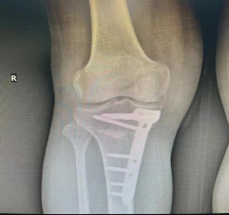

保髋、保膝手术:股骨头坏死髓心减压术、胫骨高位截骨矫形术、内外侧单髁置换术、关节镜下关节清理术。

老年髋部骨折:股骨颈、转子间骨折人工股骨头置换,老年肱骨近端骨折人工肱骨头置换,微创治疗及快速康复。